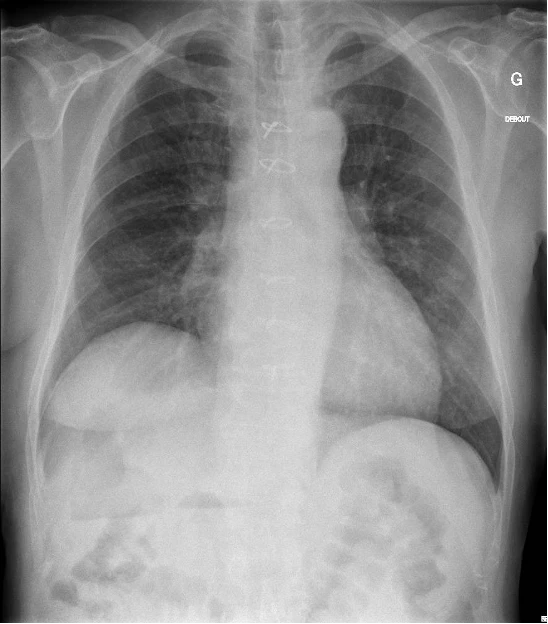

Un patient de 69 ans, connu pour maladie des anticorps anti-phospholipides et une fibrillation auriculaire anticoagulée, présente des douleurs de l’hypochondre D depuis 2 semaines, péjorées le matin et après les repas. Le patient a chuté il y a quelques mois. Au status le patient est stable, afébrile, et présente des douleurs insupportables à la palpation basi-thoracique D. L’hypochondre D est également douloureux. On retrouve de l’emphysème sous-cutané basithoracique D. Le laboratoire met en évidence : leucocyte à 34 G/​l, à prédominance neutrophilique, une élévation de la CRP200 mg/​l, des tests hépato-pancréatiques dans la norme.

Bilan radiologique complémentaire :

Le bilan radiologique suivant peut correspondre à :